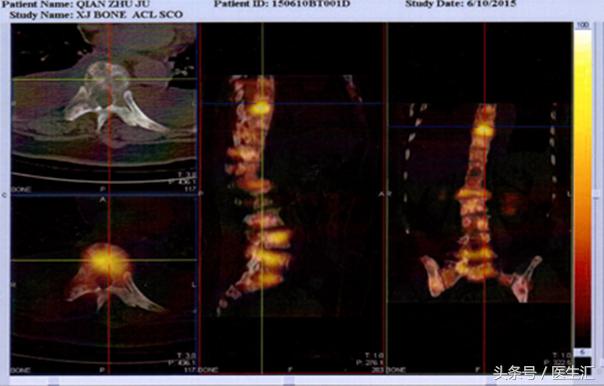

SPECT/CT(2015-6-10):腰、骶全段,双髂骨、双侧多根肋骨、

双侧肱骨、左桡骨多发混合性骨质破坏,伴骨代谢活跃,多考

虑恶性病变(肿瘤多发骨转移),伴L1椎体病理性骨折。

SPET/CT:骶骨及双侧髂骨多发骨质破坏,伴骨代谢活跃,多考虑

恶性病变(肿瘤多发骨转移)。